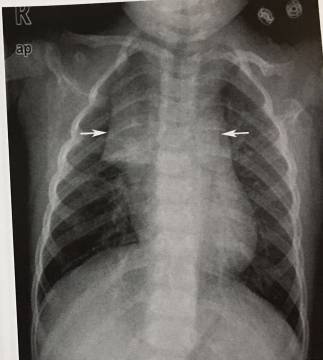

7、小儿胸腺

双侧胸腺增大使纵膈影增宽,表现为自上而下逐渐增大,向肺野突出,呈三角形,称帆样征。